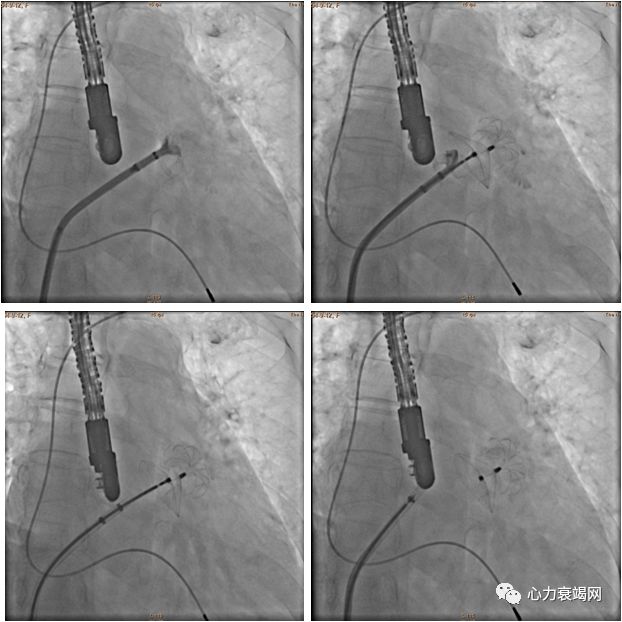

造影提示:LAA开口最大23.4mm

术前及术中TEE测量45º、60º、90º、135º提示开口最大22mm,深度38mm

选择28mm*34mm的LAmbre封堵器

术后常规双联抗血小板三个月后,单抗长久

本院第1例左心耳封堵术

术后即刻微量残余分流,直径1mm,提示成功

手术1次释放即成功,总用时90min

术后3月及12月复查TEE提示植入成功,未见残余分流

随访24个月,无严重不良事件发生